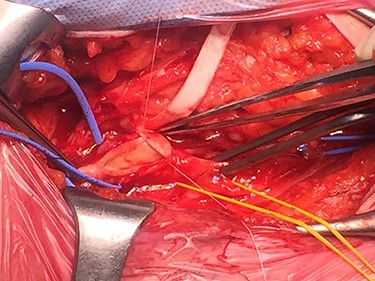

During surgical dissection of the right groin and isolation of the CFA, a jelly-like lesion of the anterior wall of the CFA was detected. The lesion caused a compression of the arterial lumen and determined its critical stenosis, with subsequent peripheral hypoperfusion leading to intermittent claudication. An accurate excision of the cystic material was performed and the clear gelatinous material leaked was collected along with a specimen of arterial wall for cytological and histological examination (Fig. 3). The surgical procedure was then completed with excision of the unhealthy arterial wall of the CFA and placement of a polyurethane patch.